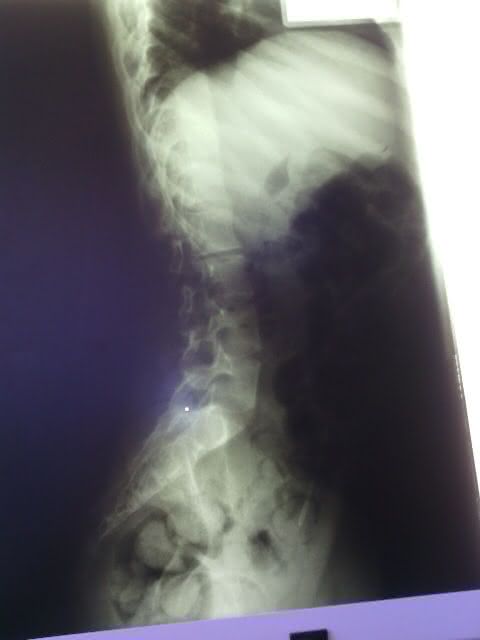

A equipe do portal visitou a residência do vigilante e da professoram que dedicam suas vidas ao pequeno Mateus Domingos dos Santos de 15 anos, que sofre de escoliose que é o encurvamento anormal da coluna vertebral, que provoca dor lombar e nas costas e pode morre caso não consiga realizar uma cirurgia nos próximos meses.

- Raio -X da coluna